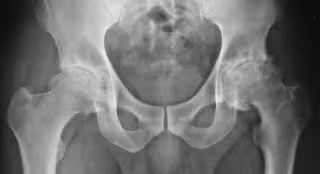

Artrosis

Artrosis - FLICKR/SILVANA CIARDULLO - Archivo